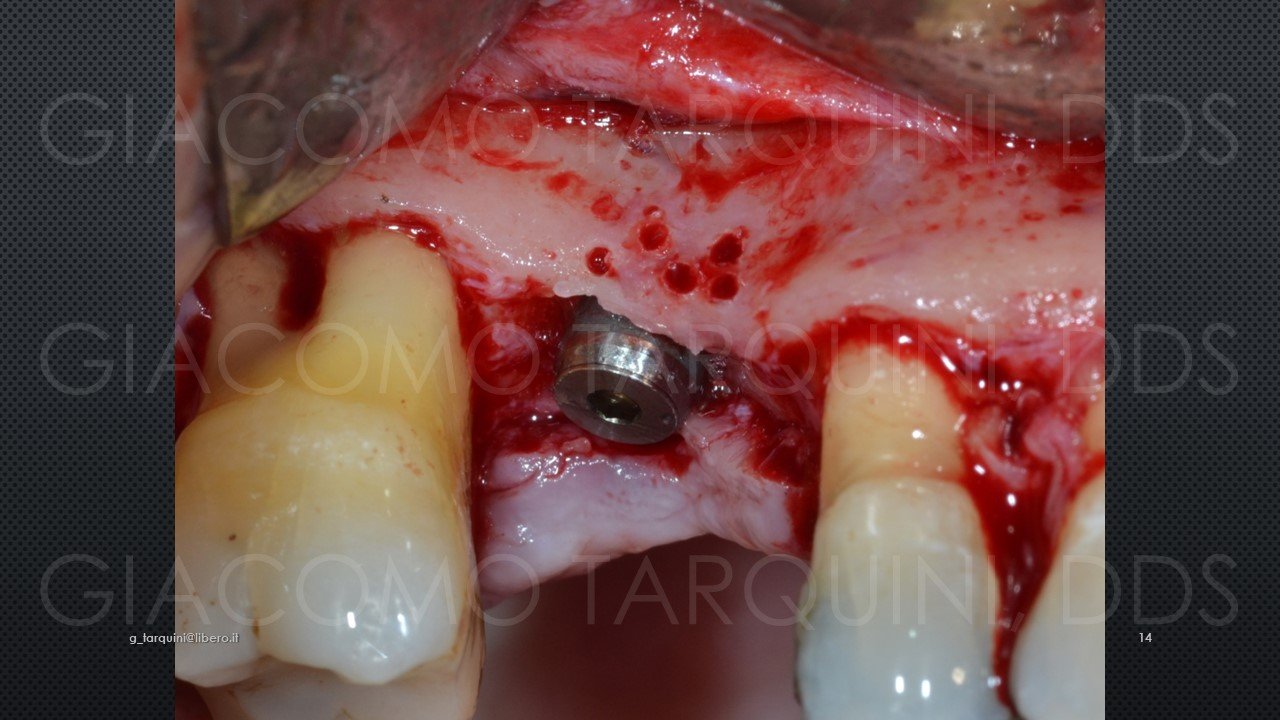

CASO CLINICO

Il caso clinico illustra una procedura di trattamento chirurgico-rigenerativo di una peri-implantite mediante decontaminazione effettuata con dispositivo «PIEZOCLEAN by Dr. Giacomo Tarquini»

Diapositiva14.thumb.JPG.b911658e8bcaa4b960e9f2056405277c.JPG